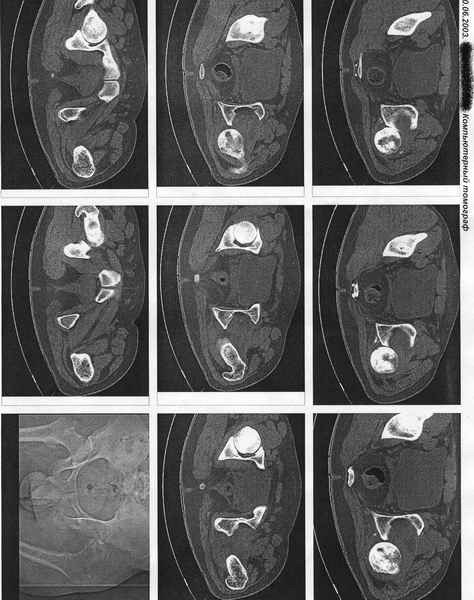

Застарелый вывих бедра

Ко мне поступил из района пациент с 7-ми месячным вывихом бедра. Возраст 25 лет. Прилагаю КТ по которой виден АНГБК. Интересно услышать ваши мнения по тактике лечения. Из эндопротезов доступен ЭСИ. С Уважением Андрей Стасюк